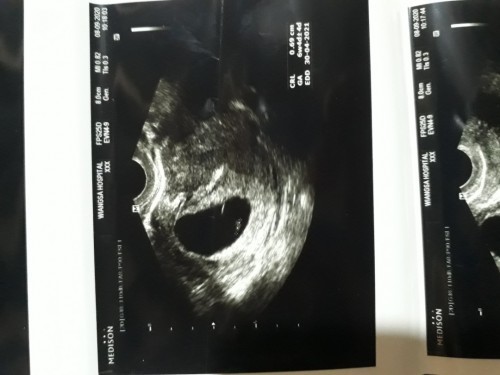

ทุกคนว่าแบบนี้จะท้องลมไหมค่ะ หมอนับได้อายุครรภ์9w แต่ในใบซาวลูกแค่6w หมอบอกว่าอาจจะท้องลม เพราะยังไม่เห่นตัวเด็ก เครียดมากค่ะตอนนี้เศร้าเลย ใครเคยตรวจไม่เจอตัวเด็กแบบนี้แต่ลูกยังอยู่มั้งค่ะ 😭😭

ของเราก็เป็นแบบนี้ค่ะ อายุครรภ์ลดลง ไม่เจอตัวเด็ก รู้ว่าตัวเองท้องลมจริงๆก็ตอนมีเลือดออกแล้วไปหาหมอ อัลตร้าซาวด์ไม่เจออะไร

รอตรวจอีก1 เดือนก็ได้ค่ะ ท้องแรกของเราเป็นท้องลมเหมือนกันค่ะ ไม่เห็นตัวเด็ก แต่มีถุงการตั้งครรภ์

อีกสองอาทิตหมอนัดไปตรวจใหม่ ถ้าไม่เจอก็ต้องยุติการตั้งครรภ์😔